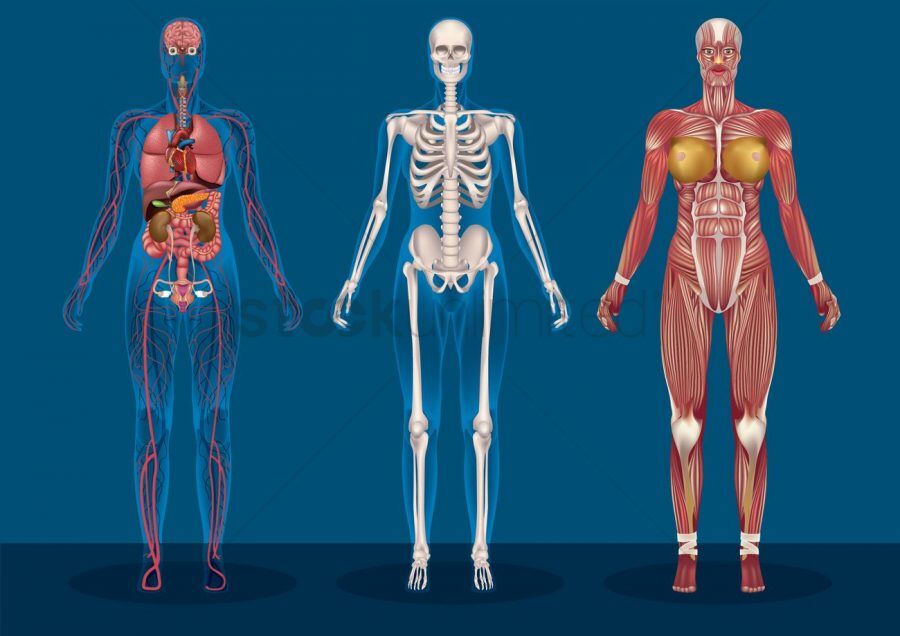

A criança se expressa e sente através de seu corpo. Por isso, é importante que ela conheça, explore e vivencie seu corpo. Esta aprendizagem não deve centrar-se unicamente nas partes externas e visíveis, mas também naquelas que a criança não vê, mas sente, e que geram nela um grande interesse e uma grande curiosidade.

A criança se expressa e sente através de seu corpo. Por isso, é importante que ela conheça, explore e vivencie seu corpo. Esta aprendizagem não deve centrar-se unicamente nas partes externas e visíveis, mas também naquelas que a criança não vê, mas sente, e que geram nela um grande interesse e uma grande curiosidade.

O corpo humano é dividido em sistemas e o instrumentador cirúrgico deve ter conhecimento básico sobre estes sistemas para que possa atuar em qualquer tipo de cirurgia. Este sistema é representado pela pele e seus anexos. A pele é o responsável pelo revestimento do corpo.

O corpo humano é dividido em sistemas e o instrumentador cirúrgico deve ter conhecimento básico sobre estes sistemas para que possa atuar em qualquer tipo de cirurgia. Este sistema é representado pela pele e seus anexos. A pele é o responsável pelo revestimento do corpo.

O corpo humano é constituído por células e substâncias intracelulares líquidas. São eles:

O corpo humano é constituído por células e substâncias intracelulares líquidas. São eles: